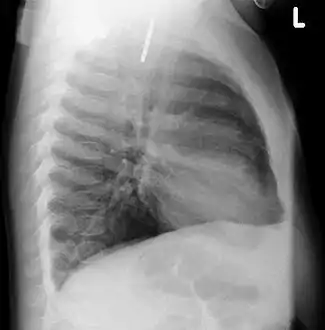

Chest radiograph showing a Venezuelan 25 cent coin lodged in the upper esophagus of a 9-year-old girl.

A coin seen on lateral CXR in the esophagus